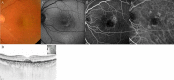

This multicenter study aimed to assess the short-term effectiveness and safety of faricimab in treatment-naïve patients with wet age-related macular degeneration (wAMD) in Japan. We retrospectively reviewed 63 eyes of 61 patients with wAMD, including types 1, 2, and 3 macular neovascularization as well as polypoidal choroidal vasculopathy (PCV). Patients received three consecutive monthly intravitreal injections of faricimab as loading therapy. Over these 3 months, visual acuity improved gradually compared to baseline. Moreover, the central foveal thickness decreased significantly at 1, 2, and 3 months compared to baseline (p < 0.0001). At 3 months after initiation of faricimab therapy, a dry macula (defined as absence of intraretinal or subretinal fluid) was achieved in 82% of the eyes. Complete regression of polypoidal lesions was observed in 52% of eyes with PCV. Subfoveal choroidal thickness also decreased significantly at 1, 2, and 3 months compared to baseline (p < 0.0001). Although retinal pigment epithelium tears developed in two eyes, there were no other ocular or systemic complications observed during the 3 months of loading therapy. In conclusion, loading therapy using faricimab resulted in improved visual acuity and retinal morphology in Japanese patients with wAMD without particular safety issues.